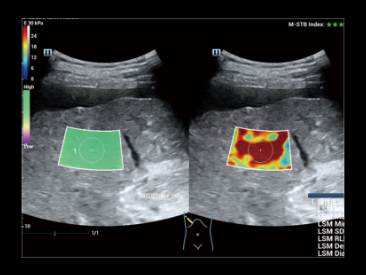

La nueva ElastografĂa Sound Touch (STE) permite tener una velocidad de cuadros mĂĄs alta en el campo, hasta 10 veces mĂĄs rĂĄpida que antes*, lo que brinda mĂĄs confianza en el diagnĂłstico clĂnico.

STE normal

STE de alta velocidad de cuadros